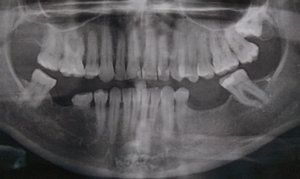

Через 2,5 дня после удаления двух зубов мудрости сдавала общий анализ крови. Некоторые показатели, которые раньше у меня были в норме, немного отклонились. Чуть повышены: гемоглобин, лимфоциты, моноциты и чуть понижены сегментоядерные.

Могло ли удаление зубов вызвать эти изменения? Или стоит начать беспокоиться и обратиться к терапевту?